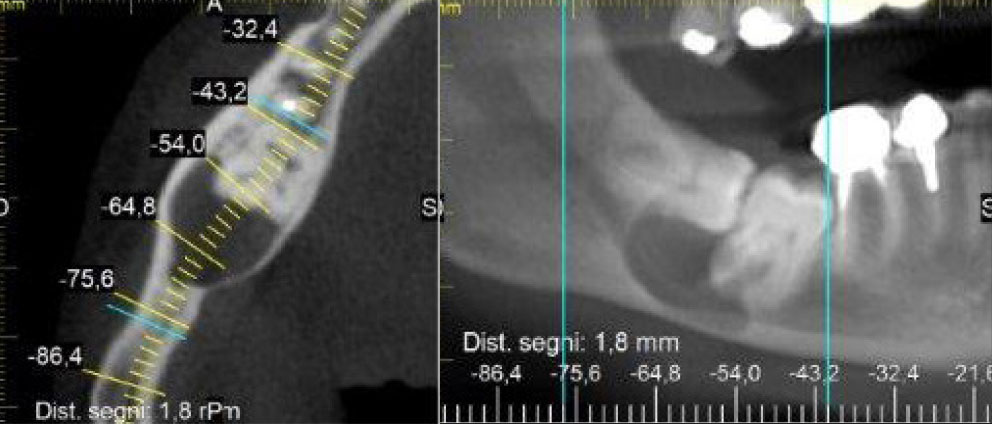

Il Prof. A. Caprioglio, Direttore della Scuola di Specializzazione, è stato invitato come guest speaker, presentando una relazione di grande rilievo su temi connessi alla distalizzazione molare con/senza l’ausilio di miniviti ortodontiche. Il suo intervento ha riscosso notevole interesse tra i partecipanti e ha rappresentato un importante riconoscimento del contributo della scuola milanese alla comunità ortodontica globale.Caso clinico del mese